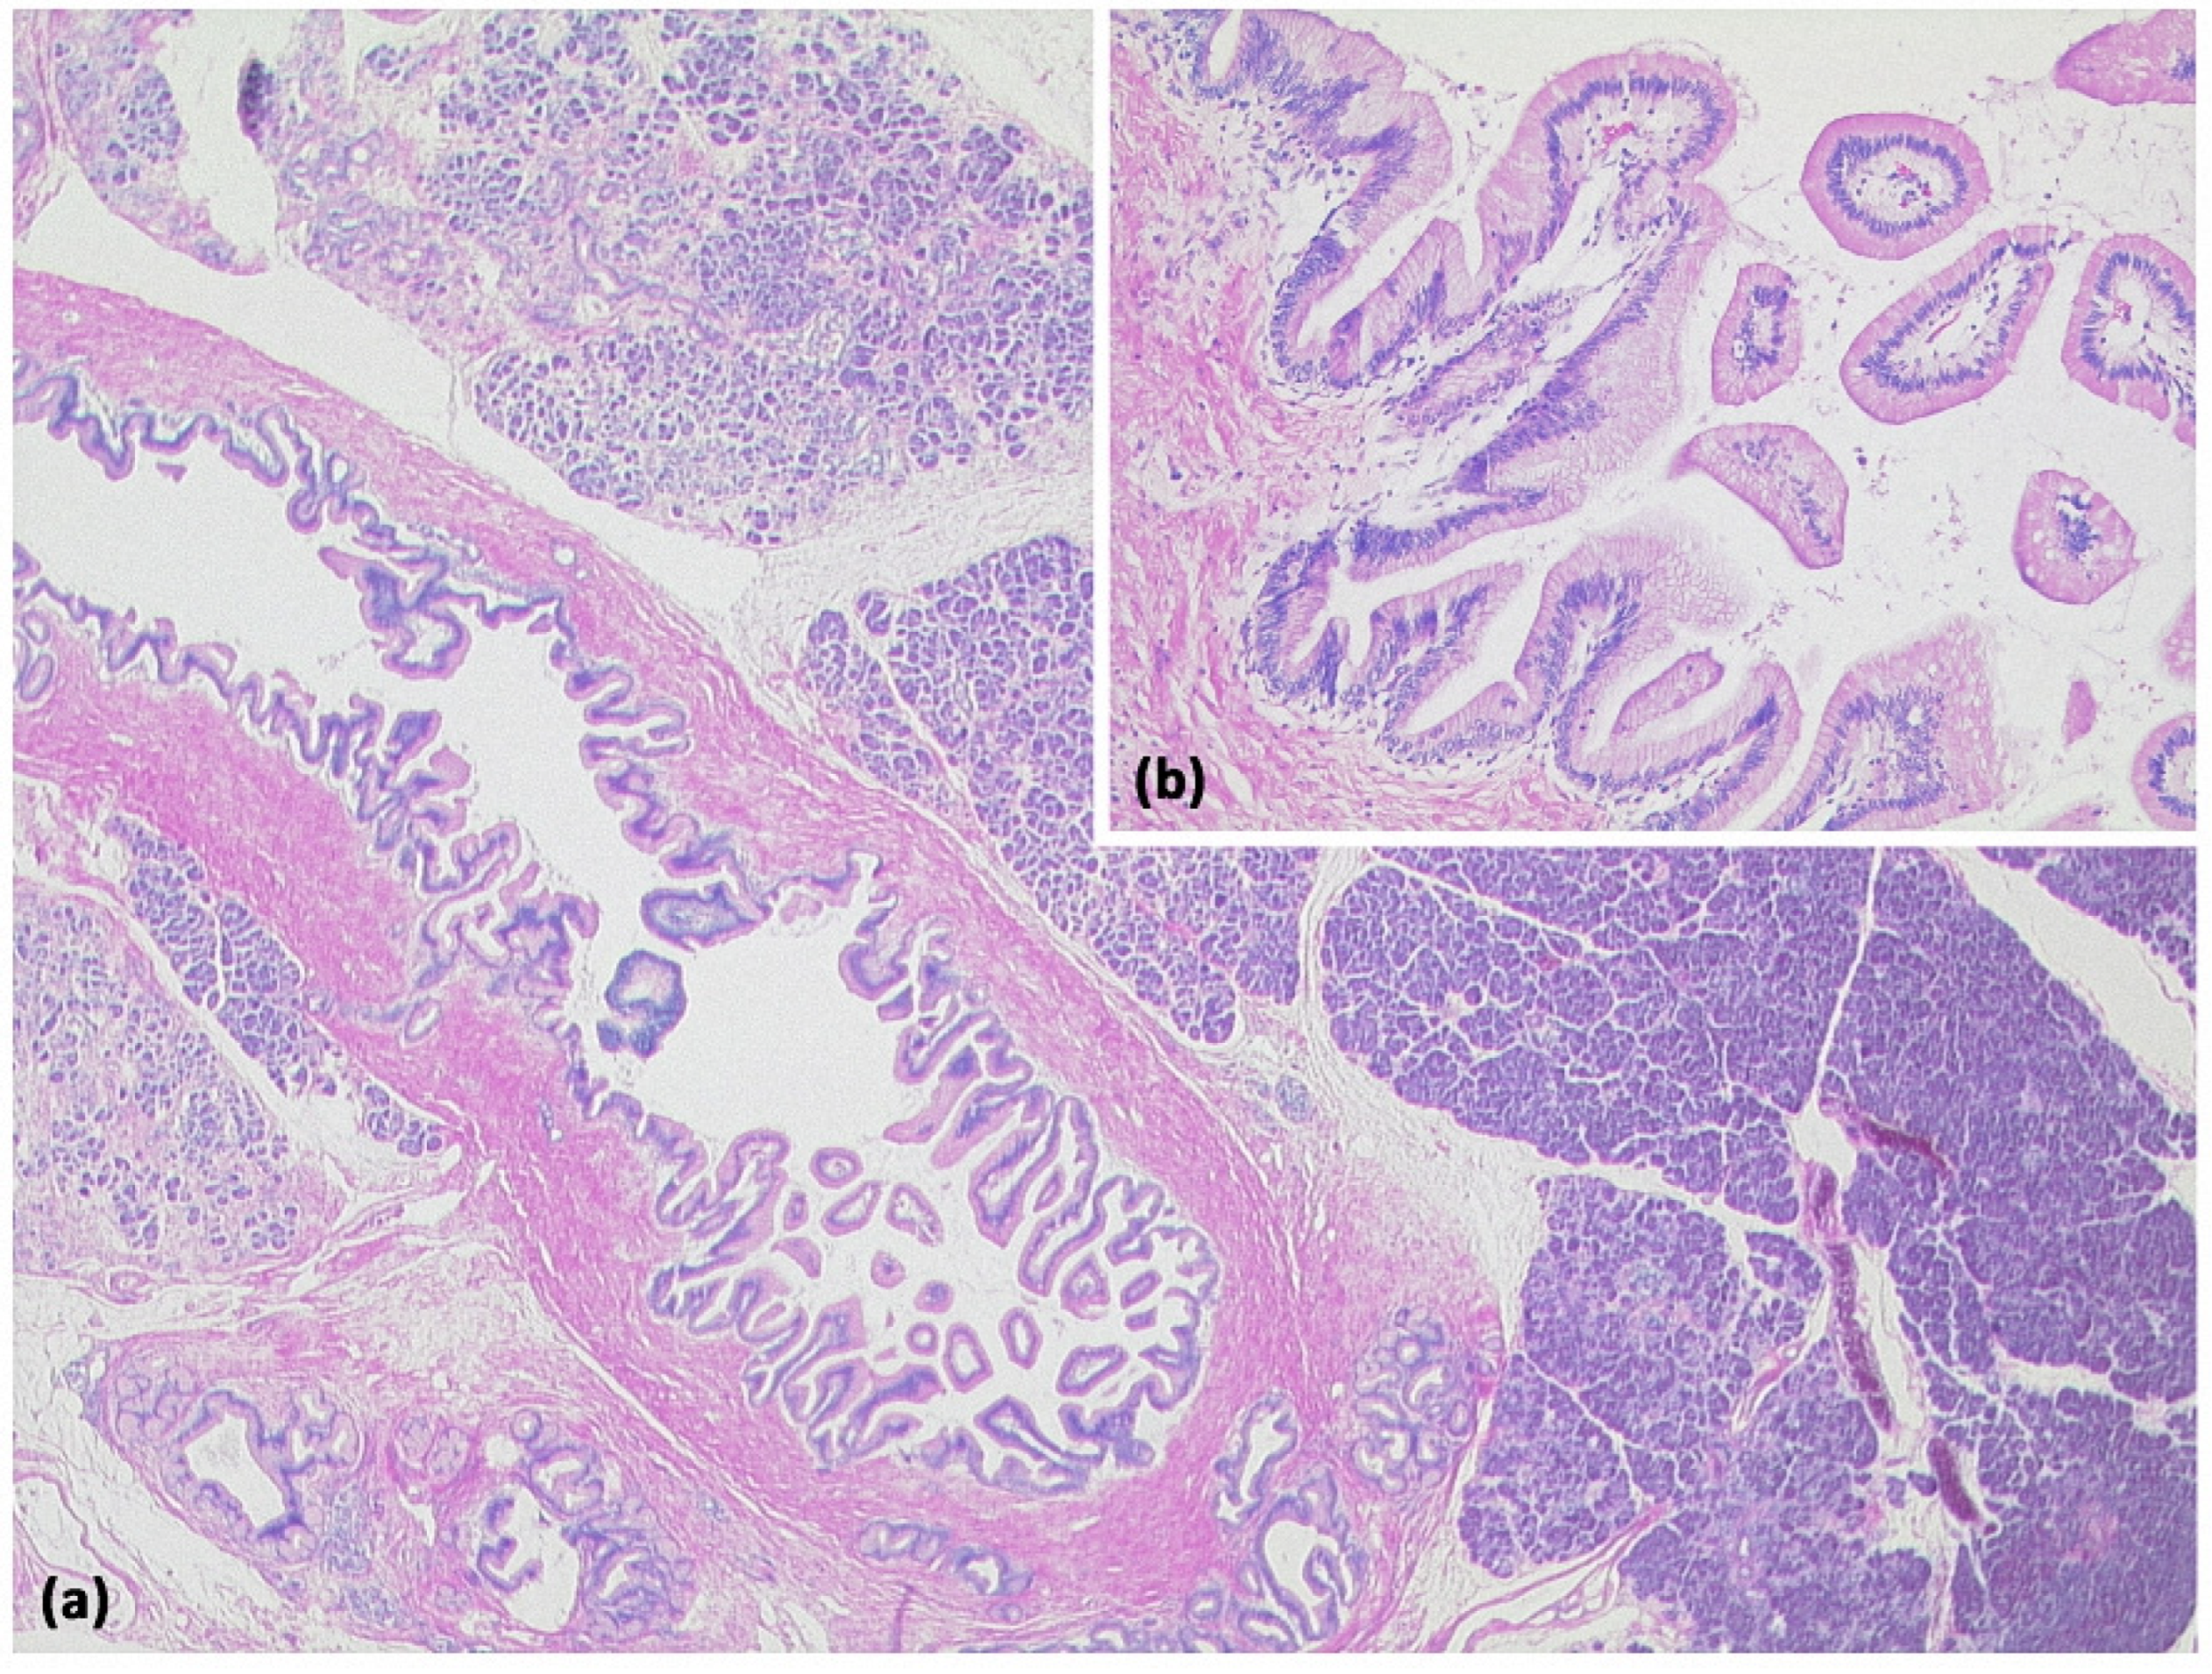

Figure 12.

Intraductal papillary mucinous neoplasm (IPMN, (a) HE, original magnification 12.5:1). Papillary proliferate of mucinous cells in a dilated pancreatic duct. Higher magnification clearly shows gastral differentiation, with no evidence of high-grade dysplasia ((b) HE, original magnification 100:1).